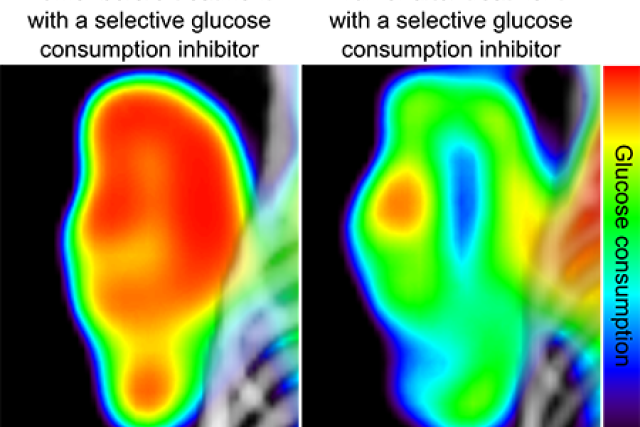

Dr. Robert Damoiseaux uses his expertise in high-through-put screening and the use of novel technologies to custom-designs experiments, coach and direct the research process, lead project teams and facilitate novel developments in scientific technology, drug discovery and research on cancer, infectious diseases and chemical and functional genomics.